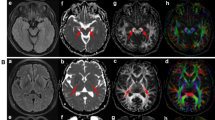

Biomarker correlation to survival, survival analyses in clinical symptom onset and genotype groups, biomarker ratios and ALSFRS-R in ALS patients. (A) Correlation between plasma NFL and survival after symptom onset stratified by spinal and bulbar symptom onset. (B) Kaplan–Meier survival analysis for spinal onset versus bulbar onset ALS patients. (C) Correlation between plasma NFL and survival after symptom onset for participants in the total ALS cohort. (D) Kaplan–Meier survival analysis between patients with no known mutation, SOD1 mutation and C9orf72HRE mutation (p-value presented for overall comparisons). (E) Ratios and correlations between plasma NFL and CSF NFL stratified for spinal onset and bulbar onset ALS patients. (F) Correlation between CSF NFL and CSF pNFH for participants in the total ALS cohort. (G) Correlation between ALSFRS-R and plasma NFL in ALS patients. (H) Correlation between ALSFRS-R and survival after symptom onset in ALS patients.

In patients in the ALS group, the concentrations of CSF NFL and CSF pNFH in patients with no known mutation, SOD1 mutation and C9orf72HRE mutation did not show any statistically significant difference (p > 0.05 for overall ANOVA). When stratifying ALS patients into SOD1 mutation subgroups, ALS patients with SOD1 D90A homozygous or heterozygous mutations combined showed significantly lower levels of CSF pNFH compared to those with SOD1 A4V heterozygous and other ALS SOD1 mutations combined (CSF pNFH; p < 0.01, CSF NFL; p > 0.05). In ALS patients, the concentrations of CSF NFL and CSF pNFH were significantly correlated (ρ = 0.797, p < 0.0001) (Fig. 3F). ALSFRS-R was negatively correlated with CSF NFL levels (ρ = −0.241, p < 0.01) but not with CSF pNFH levels (p > 0.05). Furthermore, ΔFS was correlated with CSF NFL levels (ρ = 0.355, p < 0.0001) and CSF pNFH levels (ρ = 0.346, p < 0.0001). There was no significant correlation between freezer storage time and the concentrations of CSF NFL or between freezer storage time and CSF pNFH in the patients in the ALS or ALS mimics groups (p > 0.05 for both).

Patients with bulbar onset ALS had significantly higher plasma NFL concentrations than patients with spinal onset ALS (p < 0.01). There was no statistically significant difference when comparing the levels of plasma NFL of ALS patients with truncal onset to those of ALS patients with spinal onset or bulbar onset (p > 0.05 for both). In ALS patients, the concentrations of plasma NFL were significantly correlated with CSF NFL (ρ = 0.773, p < 0.0001) and CSF pNFH (ρ = 0.696, p < 0.0001). When stratified by the region of symptom onset, patients with spinal onset or bulbar onset ALS both showed a higher correlation between plasma NFL and CSF NFL levels (ρ = 0.790, p < 0.0001 and ρ = 0.762, p < 0.0001, respectively) (Fig. 3E) than all ALS patients as a whole group. The plasma NFL concentration was significantly higher in ALS patients with C9orf72HRE mutations than in patients with SOD1 mutations (p < 0.05). No significant difference in plasma NFL concentration was found by comparing ALS patients with no known mutations to ALS patients with SOD1 or C9orf72HRE mutations (p > 0.05 for both). When stratifying ALS patients into spinal and bulbar onset groups, statistically significant differences in plasma NFL concentrations in spinal onset ALS patients were observed when comparing patients with C9orf72HRE mutations to both patients who were SOD1 mutation carriers (p < 0.01) and ALS patients with no known mutations (p < 0.05); however, there was no statistically significant difference among different genotype groups in bulbar onset ALS patients (p > 0.05 for overall ANOVA). ALS patients homozygous or heterozygous mutation for the D90A SOD1 mutation combined showed significantly lower plasma NFL concentrations compared to patients with SOD1 A4V and other SOD1 mutations combined (p < 0.01). Plasma NFL concentration was negatively correlated with ALSFRS-R (ρ = −0.328, p < 0.0001) (Fig. 3G) and positively correlated with ΔFS (ρ = 0.426, p < 0.0001). There was no statistically significant correlation between plasma NFL concentrations and freezer storage time from samples collected from ALS patients and ALS mimics (p > 0.05 for both).

There was no significant difference in the NFLCSF/pNFHCSF ratio among ALS patients, ALS mimic groups and controls (p > 0.05 for overall ANOVA) or between ALS symptom onset groups (p > 0.05 for overall ANOVA). Bulbar onset ALS patients had a significantly higher NFLplasma/NFLCSF ratio (0.046 ± 0.021) than spinal onset ALS patients (0.034 ± 0.016) (p < 0.01) (Fig. 3E). Although patients with C9orf72HRE mutations had notably higher NFLCSF/pNFHCSF ratios (0.302 ± 0.129) than patients with SOD1 mutations (0.242 ± 0.111) (Fig. 3F), this difference did not reach statistical significance (p > 0.05 for overall ANOVA).